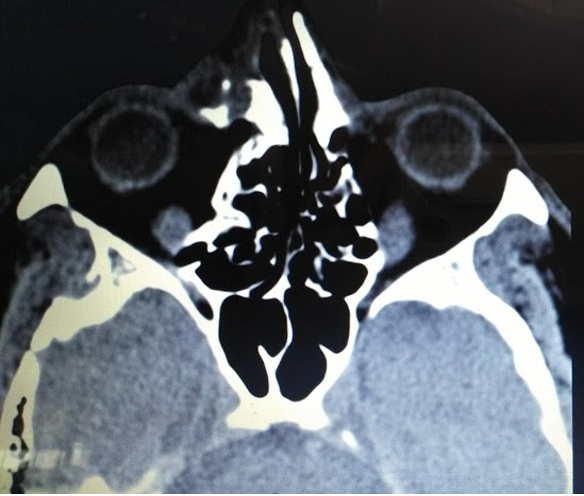

Paciente masculino de 49 años de edad procedente de área urbana refiere inicio de enfermedad actual de 1 día de evolución cuando presentó dolor y disminución de la agudeza visual posterior a trauma directo con objeto expedido a alta velocidad, por lo que consulta.